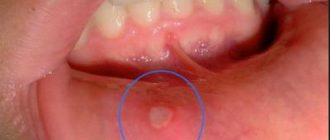

Стоматит – рецидивуюче запалення слизового епітелію, який вистилає ротову порожнину, прикореневу область, слизову губ.

Стоматит на губах — запалення слизової оболонки ротової порожнини, локалізується на внутрішній поверхні губ,

Стоматит — запальний процес на слизовій ротової порожнини. Діагноз «стоматит» ставиться пацієнтам різних вікових